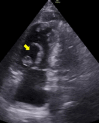

Keywords: POCUS; pulmonary embolism; thrombus in transit.